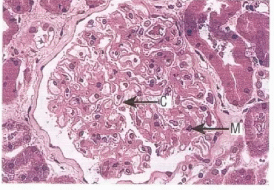

Бүйректің биопсия

Бүйректің биопсия: Капиллярлы ілмектер (С) диффузды қалыңдаған, иммунды комплекстердің субэпителиальді жиналуы (М). Қорытынды: мембранозды нефропатия.

Бүйректің биопсия интерпретациялау |

Капиллярлы ілмектер (С) диффузды қалыңдаған, иммунды комплекстердің субэпителиальді жиналуы (М). Қорытынды: мембранозды нефропатия. |

Алдын ала негізделген диагноз, сонымен қатар гипергликемия, гипопротеинемия, гипоальбуминемия, гиперхолестеринемия; ЖЗА-3 г/л-ден жоғары протеинурия (4,8 г/л),бүйректердің өлшемі ұлғайған (паренхиманың ісінуі), асцит,капиллярлы ілмектер (С) диффузды қалыңдаған, иммунды комплекстердің субэпителиальді жиналуы (М) мына диагноз қойылды: қант диабеті 2 тип, орташа ауырлықта, декомпенсация. Диабеттік нефропатия 4 дәрежесі. Артериальді гипертензия 2 дәрежесі, қауіп 4. ҚАЖ0. |